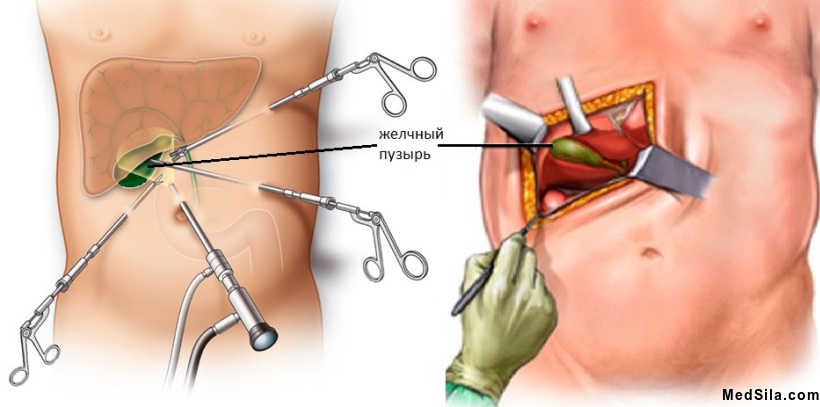

При тяжелых формах холецистита, частых его обострениях рекомендована операция: холецистэктомия (удаление желчного пузыря). Чаще операции назначаются в плановом порядке в межприступный, так называемый «холодный» период, иногда операции проводятся в остром периоде по жизненным показаниям: при расслоении или разрывах стенки пузыря.